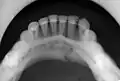

Nondisplaced fracture of the mandible